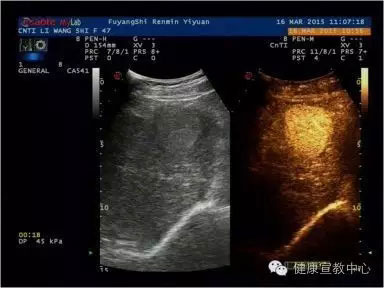

(甲乳分級診斷彈性評估技術(shù))

(超聲造影輔助分類)

(肝臟超聲造影)